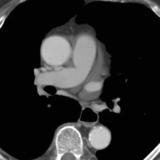

Part'l absc peric CT

Date: 07/23/2006

Views: 3171